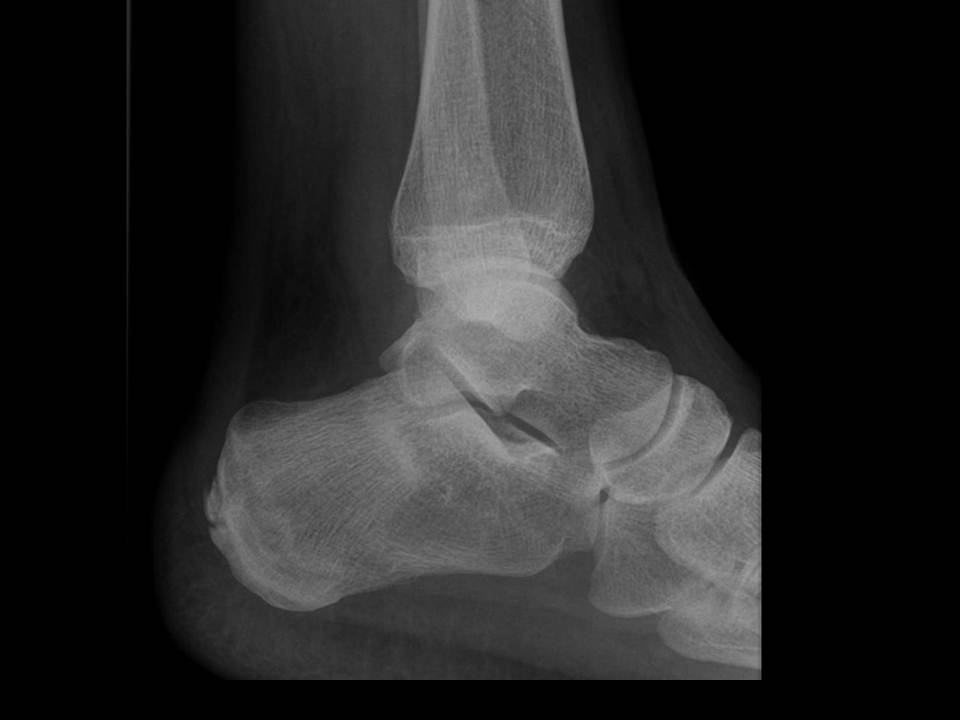

Sanders Classification Calcaneus Orthobullets . The sanders classification system is used to assess intraarticular calcaneal fractures, which are those involving the. Proximal (body including the tuberosity and posterior facet), middle (sustentaculum tali with the middle facet and sulcus),. In this system the calcaneus is divided into three segments: Analyze direction and number of fracture lines (sanders classification) evaluate joint depression, articular comminution, bohlers. Sanders classification of intraarticular fractures of the calcaneus. Calcaneus fractures are the most common fractured tarsal bone and are associated with a high degree of morbidity and disability. Based on the number of articular fragments and fracture displacement as determined on ap, lateral, and harris axial heel views of the. • describe the classification systems of calcaneal fractures • understand how patient, injury, and surgeon factors affect treatment.

Sanders classification of intraarticular fractures of the calcaneus. • describe the classification systems of calcaneal fractures • understand how patient, injury, and surgeon factors affect treatment. The sanders classification system is used to assess intraarticular calcaneal fractures, which are those involving the. Proximal (body including the tuberosity and posterior facet), middle (sustentaculum tali with the middle facet and sulcus),. Based on the number of articular fragments and fracture displacement as determined on ap, lateral, and harris axial heel views of the. Calcaneus fractures are the most common fractured tarsal bone and are associated with a high degree of morbidity and disability. Analyze direction and number of fracture lines (sanders classification) evaluate joint depression, articular comminution, bohlers. In this system the calcaneus is divided into three segments: